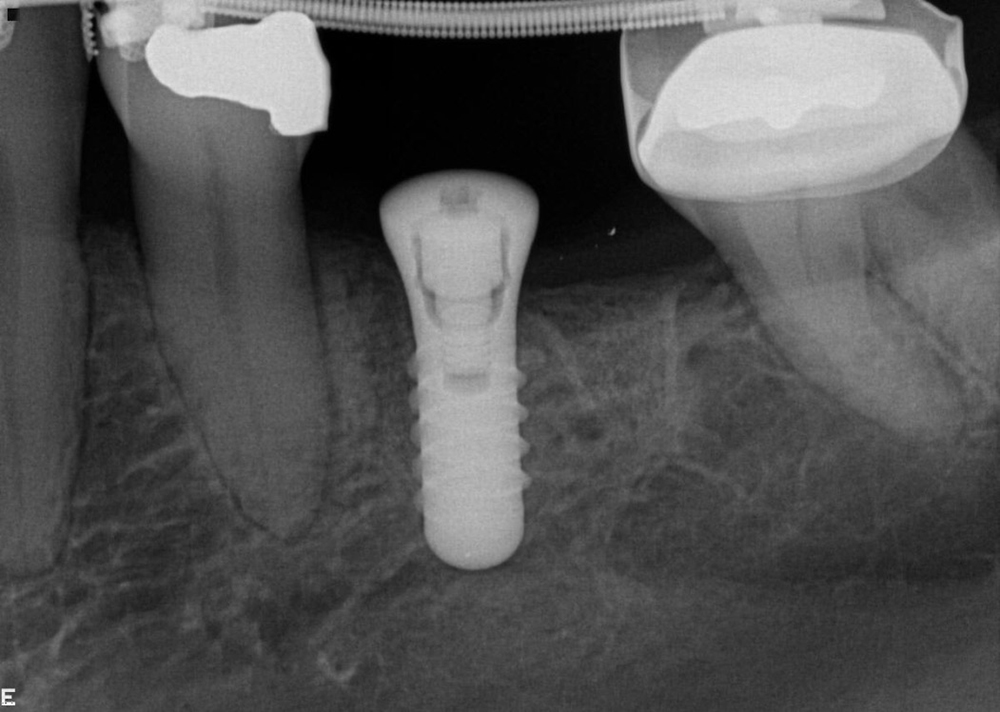

Our non-clinical goals in this case were to convey to the patient that her problems were an interdisciplinary, complex issue that had been ongoing and worsening for many years. Our solution to these problems would require the collaborative efforts of a team of dentists. The objective clinical goals were to orthodontically move her teeth into a less restrictive position and create room for restoration of lost tooth structure. Implants would be used not only to replace missing teeth but to provide orthodontic anchorage to facilitate movements that would not be possible with conventional orthodontics. Our final restorative goals were to reestablish ideal form and function, creating an occlusion that was stable and comfortable, enabling long term dental health. As her desires were specifically not to address esthetics, we were clear esthetic improvements were the result of correcting form and function. Of note is the fact that this case, from the restorative and surgical standpoint, was to be accomplished, with few small exceptions, entirely digitally.

In considering a treatment plan for our patient, it is important to note that in our initial information gathering she was clear she had no esthetic concerns. Further, her desires were single tooth in nature, specifically to replace her missing lower molar teeth. The most challenging aspect of this plan was communicating to the patient what her true problem was and having her accept that the problem, if left untreated, was a challenge to her dental health for life. She must also understand the solution to the problem and to appreciate that comprehensive care with orthodontics and restorative dentistry is to solve a long standing functional and structural problem. Esthetic improvements are a consequence of restorative and structural improvements, not a primary driver in the plan. In our multiple consultation appointments, we allowed the patient to ask as many questions as she needed answered. In short, it took her about six months to overcome the single tooth mindset that she had been taught by her previous dental experiences. Photographs were a significant component in our explanation. They demonstrated the excessive wear resulting in the extractions and were an indicator of what she should expect if she chose only to have the missing lower molars replaced. The orthodontic consultation was a key in her accepting care. An opinion from one of our specialist colleagues, another set of eyes if you will, added support for our recommendations. The plan ultimately accepted by the patient was altered from our originally proposed plan per the patient’s request to only restore the mandibular posterior teeth leaving the mandibular anterior teeth unrestored. With this compromise we still felt we could achieve acceptable anterior function. That altered our overall plan in two ways. First, the orthodontic plan would now not include intrusion of the lower anterior teeth as the incisal edges will dictate tooth position, not the gingival levels. The orthodontist would place the incisal edges of these teeth in ideal position. And second, when restoring the mandibular posteriors after placement of the maxillary restorations, we will not alter the VDO.